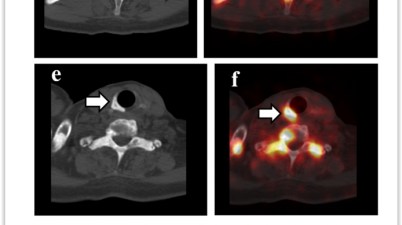

Ga-68 DOTATATE PET/CT Görüntülemede Normal Varyantlar, Tuzaklar ve Artefaktlar

Özet Bu makale, nöroendokrin tümörlerin (NET) görüntülemesinde kullanılan Ga-68 DOTATATE PET/CT’nin normal varyantlarını, tuzaklarını ve artefaktlarını incelemektedir. Ga-68 DOTATATE, hücre […]